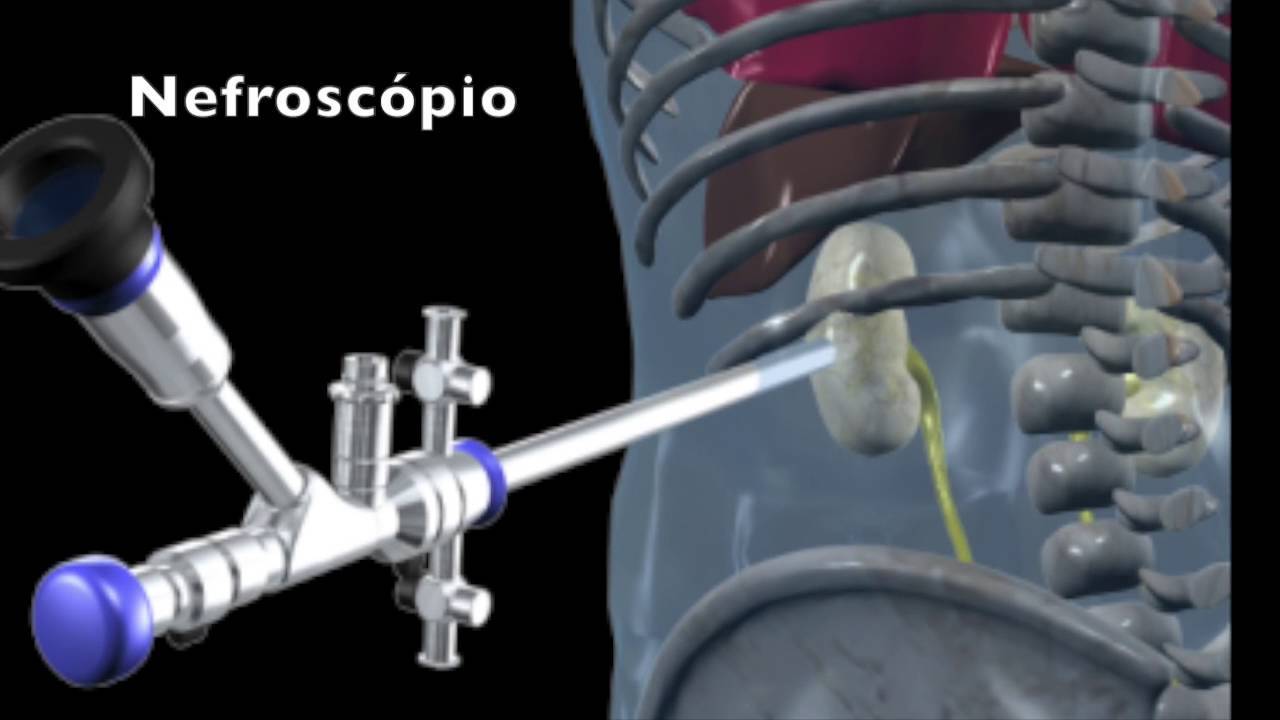

- Nefrolitotripsia Percutânea

Quais as indicações de Nefrolitotripsia Percutânea na Nefrolitíase Aguda?

- Cálculo proximal e > 2 cm

- Cálculo no Polo Renal Inferior